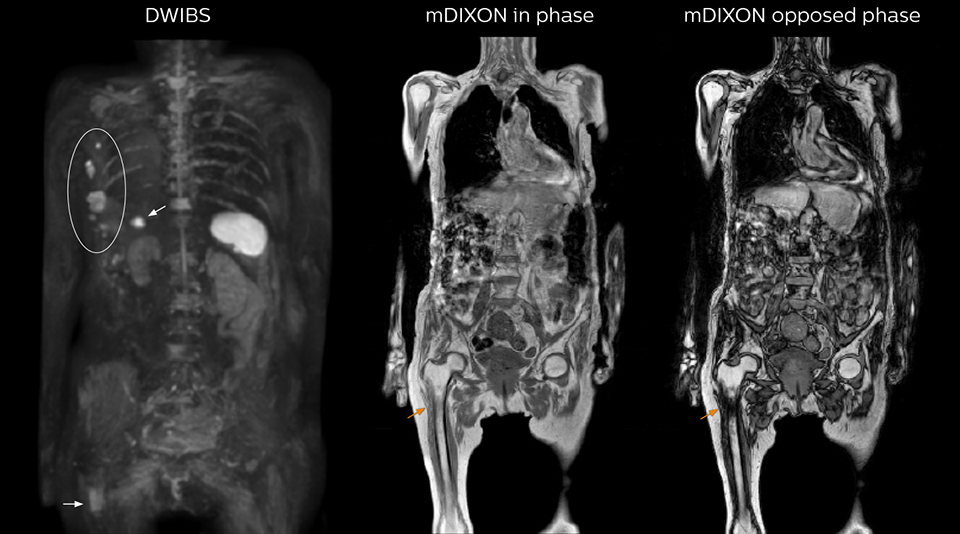

Radiologist Hiroshi Nobusawa, MD, PhD, explains that the coronal DWIBS protocol for whole body DWI is excellent for visualizing lesions in oncology patients. “About 90% of the DWIBS exams are done in this type of patients. The remainder of DWIBS exams are performed to gain information in cases of fevers of unknown origin,” he says. in image acquisition and postprocessing algorithms.”“mDIXON TSE sequences allow simultaneous characterization of morphological changes from the in-phase T2-weighted images and visualization of edematous changes, thanks to the water T2-weighted images from the same acquisition. Anatomical and morphological considerations could be a partial or complete ligament tear, a bony avulsion or hematoma.” “For soft tissue assessment mDIXON brings similar benefits. For example in one T2-weighted mDIXON TSE acquisition, having the multiple contrasts helps us assess abnormalities in peripheral nerves fascicles, which may be due to anatomical or inflammatory changes..” “In peripheral joints, we get good image quality in difficult areas with mDIXON TSE. Fat suppressed images appear homogeneous over the entire image, even with large coverage at 3.0T – for instance in scapular or hip girdles – or in the bearing areas or around metal prostheses*, where fat suppression is often deficient with STIR or spectral fat suppression, causing diagnostic difficulties. If a diagnostic image is right the first time, we don’t need to repeat or add a sequence.” “mDIXON TSE sequences allow simultaneous characterization of morphological changes from the in-phase T2-weighted images and visualization of edematous changes, thanks to the water T2-weighted images from the same acquisition. Anatomical and morphological considerations could be a partial or complete ligament tear, a bony avulsion or hematoma.” “For soft tissue assessment mDIXON brings similar benefits. For example in one T2-weighted mDIXON TSE acquisition, having the multiple contrasts helps us assess abnormalities in peripheral nerves fascicles, which may be due to anatomical or inflammatory changes..”

“The DWIBS sequence’s value in oncology cases is due to the high contrast it creates between lesions and surrounding tissue. Whole body DWI is requested by physicians who need to clarify TNM staging or determine therapeutic strategies, oncologists in need of diagnosis or follow-up scans, surgeons who need to see the presence of distant lesions that are sometimes difficult to detect by CT before surgery, and urologists for the evaluation of bone lesions, and the effect of chemotherapy and radiotherapy.”

“mDIXON FFE allows us to quickly get information we need to assess the presence of fat. That gives us more information when we need to diagnose bone lesions, and when we are asked to judge fat-containing lesions such as hepatocellular or renal carcinoma,” Dr. Nobusawa says. “The mDIXON fat images can help us to differentiate fatty bone marrow from bone lesions. This is especially useful in elderly people, who tend to have fattier bone marrow. The water images provide a high signal-to-noise ratio in the intestinal canal, which is valuable for visualizing lesions in the colon,” he says.

Kawasaki Sawai Hospital’s whole body protocol also includes an mDIXON FFE sequence. Because mDIXON provides images for four contrast types – water only, fat only, in-phase and out-of-phase – from a single acquisition, it is useful in many ways.

“In-phase and out-phase sagittal T1-weighted FFE images help us to visualize and further characterize bone lesions such as metastasis and bone-marrow hyperplasia that have high signal on DWI. These images are also used throughout radiotherapy, to monitor changes in the fatty bone marrow.”